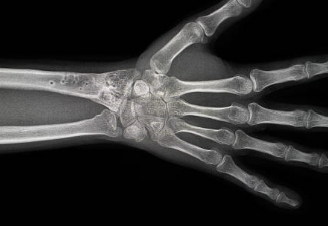

약지 손가락 통증의 원인 및 예방법

약지 손가락 통증의 원인과 예방법에 대해 알아볼게요.